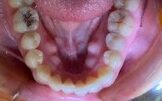

●詰め物や被せ物の段差

詰め物や被せ物を作るとき、詰め物や被せ物の種類によって削り方を変えるなどして、歯と段差ができるだけ生じないように気をつけて作ります。

しかし、どれだけ精密に作ったとしても、わずかな段差が生じるのは避けられません。

虫歯の原因である虫歯菌の潜むプラークは、こうした段差を好むので、詰め物や被せ物の段差はプラークの温床となりやすく、虫歯の再発する原因となってしまいます。

●コンポジットレジンの劣化

小さな虫歯の治療では、現在、コンポジットレジンというプラスチック材料がよく使われています。

コンポジットレジンは、ベースレジンとフィラーという粉末成分を組み合わせて作られているのですが、時間が経つとフィラーが少しずつ取れていき、表面に目に見えないような穴が開きます。

この部分もプラークがつきやすく、やはり虫歯が再発しやすくなります。